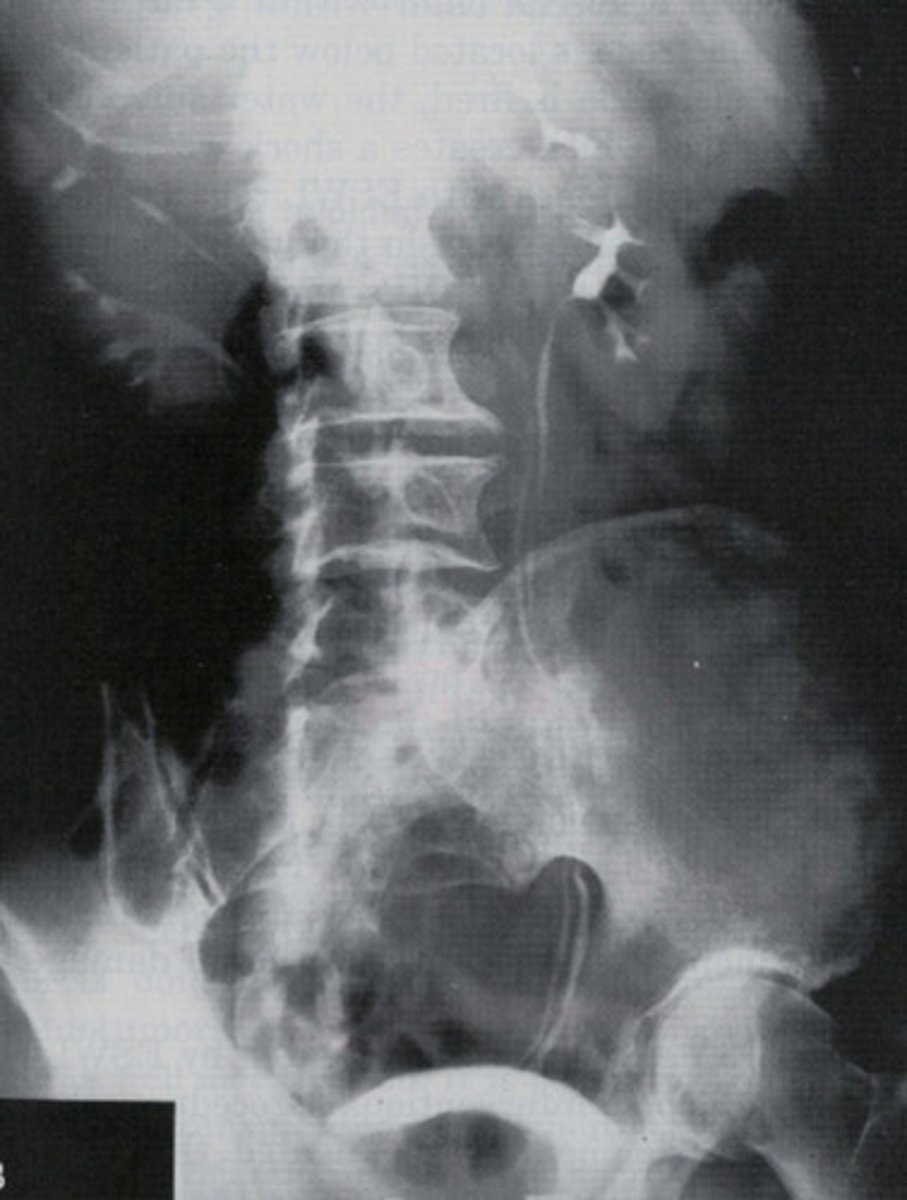

- Wilms Tumor / Nephroblastoma

- Infants and children

- What type of renal neoplasm arises from the embryonic renal tissue that distorts the calyces and creates a vine like blood supply?

- This is the most common abdominal neoplasm in who?

- Neuroblastoma

- second / children

- What type of abdominal neoplasm arises from the adrenal gland (endocrine system) and pushes down on the kidney?

- This is the _________ most common abdominal neoplasm in whom?